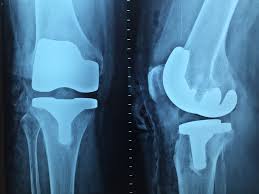

- Cirurgia Ortopédica: Envolve procedimentos cirúrgicos para corrigir deformidades, reparar lesões e restaurar a função das articulações. Inclui cirurgias de substituição articular, como artroplastias de quadril e joelho.

- Próteses e Implantes: A evolução dos materiais e técnicas de implantação tem melhorado significativamente os resultados de cirurgias de substituição articular, proporcionando maior durabilidade e funcionalidade às próteses.